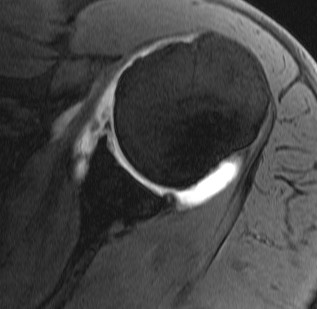

MRI

Anterior labral tears

Normal humeral insertion of IGHL on left, HAGL with discontinuity of J sign on right